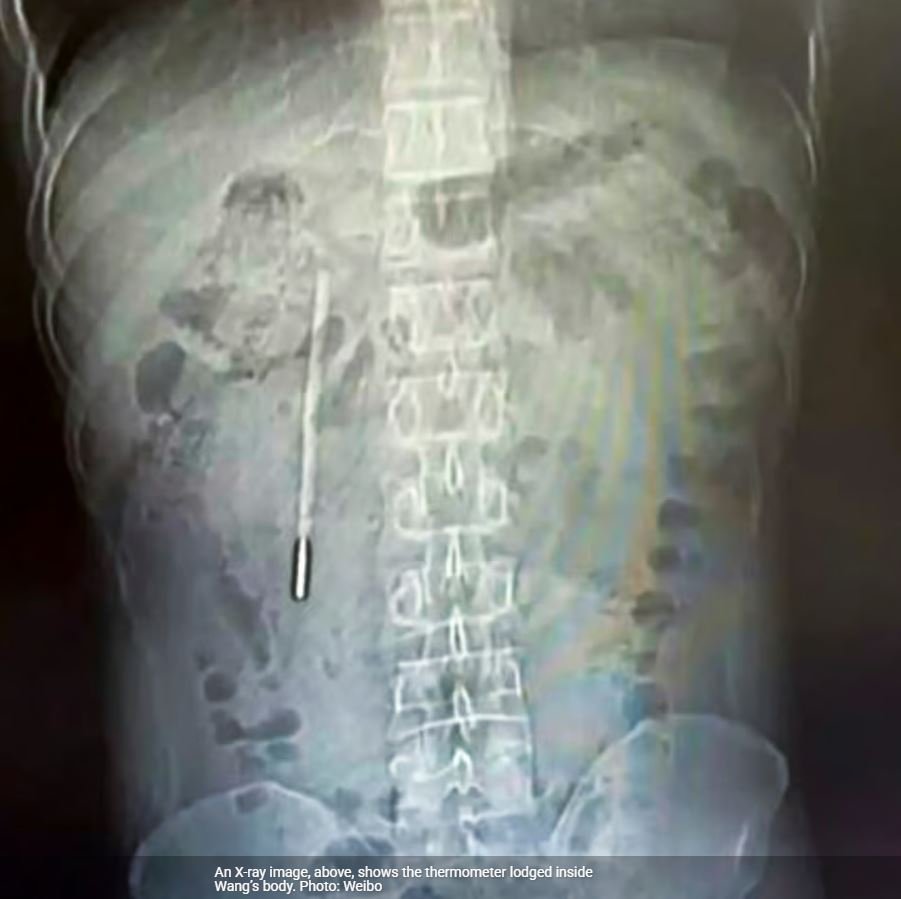

Οι ακτινογραφίες αποκάλυψαν την παρουσία του θερμόμετρου υδραργύρου στο δωδεκαδάκτυλο

Σύμφωνα με την South China Morning Post , στο νοσοκομείο ο άνδρας έκανε απεικονιστικές εξετάσεις (ακτινογραφίες), οι οποίες αποκάλυψαν την παρουσία του θερμόμετρου υδραργύρου στο δωδεκαδάκτυλο.

Η άκρη του θερμόμετρου πίεζε το εντερικό τοίχωμα, αυξάνοντας σημαντικά τον κίνδυνο διάτρησης και σοβαρής εσωτερικής αιμορραγίας.